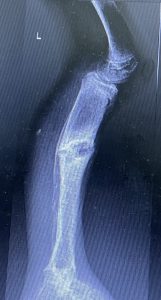

Bei der 3jährigen Chantal (Name geändert) hatten die ruandischen Kollegen einen riesigen Sequester aus der Tibia (Schienbein) entfernt. Nach Abklingen aller Infektzeichen bestand nun die Indikation den entstandenen Defekt mit einem Fibulatransplantat zu überbrücken.

Dr. Feltes und Dr. Weber hatten für heute geplant die kleine Chantal (Name geändert) zu operieren. Geplant war den Tibiadefekt rechts mit einem Fibulatransfer zu decken. So gegen 13 Uhr wurden die beiden in den OP gerufen.

Das war die Ausgangssituation.